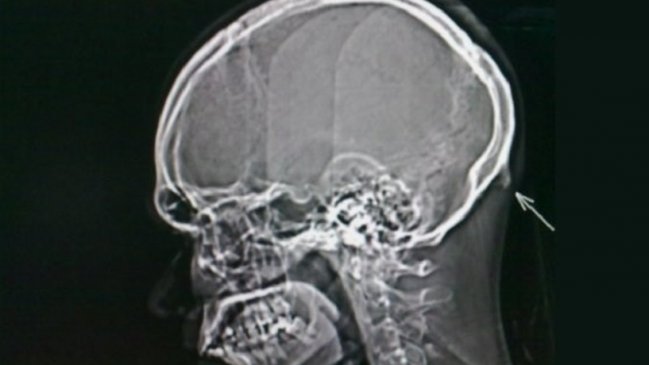

De acuerdo con el estudio, se trata de un "cuerno" de hueso que está apareciendo en las generaciones más jóvenes encima del cuello y en la base del cráneo.

La investigación fue realizada por el Dr. David Shahar y el académico Mark Sayers en 2016, cuando analizaron las "protuberancias occipitales externas" en las radiografías de 218 pacientes jóvenes (entre 18 y 30 años).

De esa cifra, un 41 por ciento tenía el "cuerno" con algunos superiores a 20 milímetros y el mayor de 35 milímetros correspondiente a un hombre.